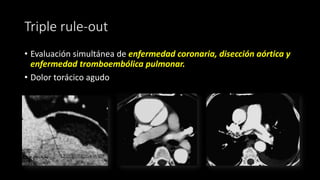

Triple rule-out

• Evaluación simultánea de enfermedad coronaria, disección aórtica y

enfermedad tromboembólica pulmonar.

• Dolor torácico agudo